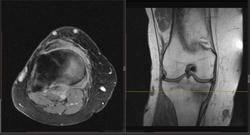

Женщина 1949 года рождения, жалуется на боли в правом коленном суставе в течении 2-х недель, травму категорически отрицает. Выполненна МРТ и рентгенография. Дайком. Какие версии?

Сам думаю о начальных проявлениях инфаркта костного мозга. Слева был перелом средней трети ББК.

Так, вот, хотел автора попросить - если возможно, указать на скане линию этого перелома.

Формирующаяся линия перелома на сканах МРТ указана.

Благодарю за стрелочки! Смотрел, не поверил, отчего такой изломанный вид имеет линия перелома. А книга Ваша говорит, что это нормально для МРТ. Угу. Понял. Рентгенологически, значит, 3 стадии мы не видим.(

Скажите, а периостальную реакцию Вы здесь тоже наблюдаете?.. Если не затруднит... - стрелочкой не покажите?..